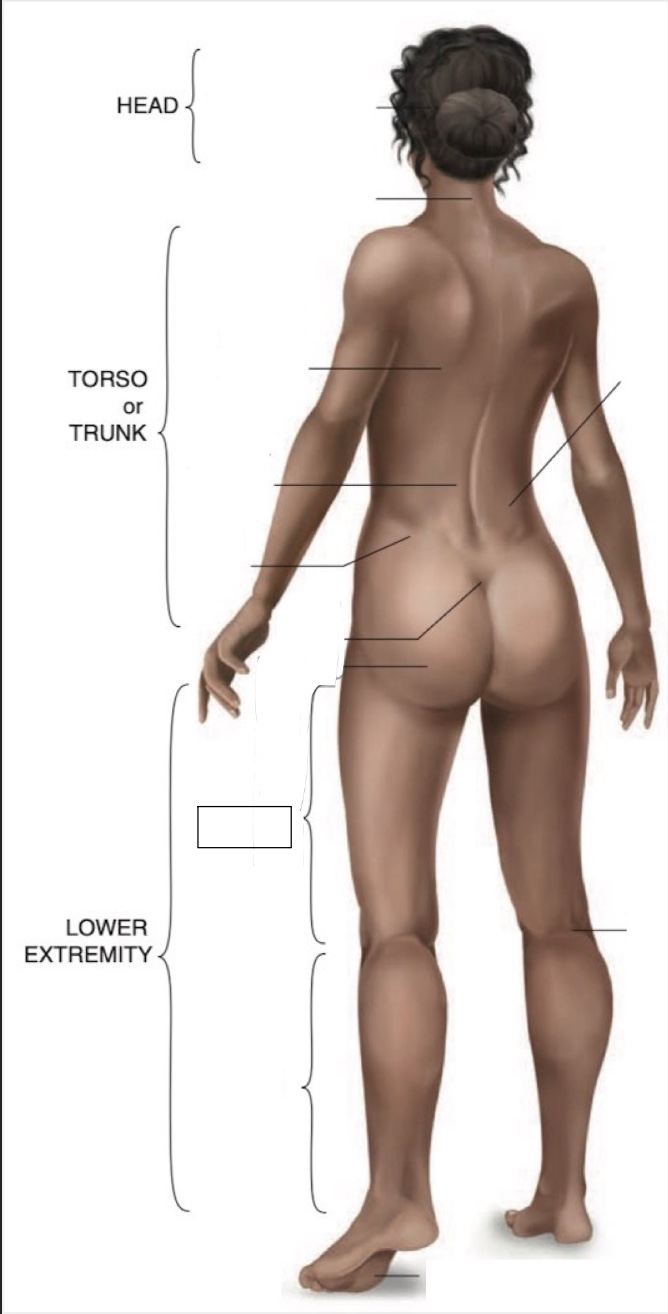

Occipital region

Cervical region

Inferior angle of scapula

Lumbar region

Iliac crest

Sacral region

Buttock

Thigh

Leg

Flank

Popliteal region